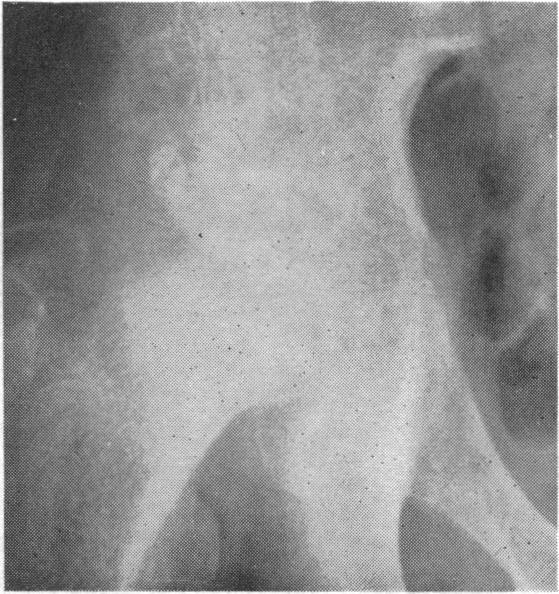

Place of surgery in early stages of acute osteomyelitis.

Br Med J. 1962 May 26;1(5290):1440-4. doi: 10.1136/bmj.1.5290.1440.